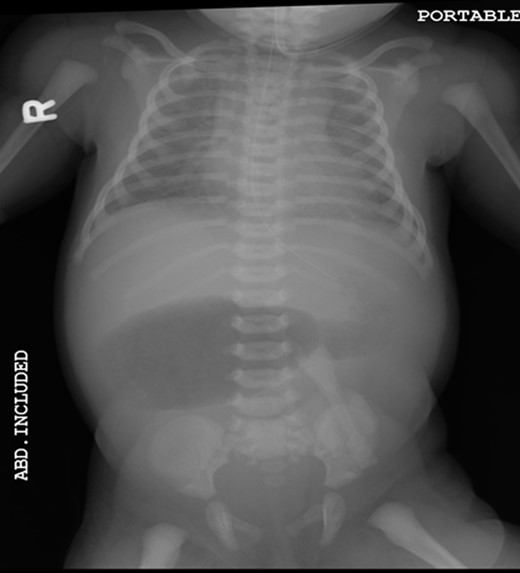

A 1-day-old baby girl, born by normal spontaneous vaginal delivery, was evaluated for abdominal distension and history of having not passed meconium. An abdominal X-ray was suspicious for malrotation (Fig. 1). The patient did not have any evidence of sepsis. An echocardiogram ruled out any congenital cardiac anomalies.

Pre-operative abdominal x-ray showing a gastric and duodenum distention with paucity of small bowel gas distally, suggesting duodenal atresia and malrotation.